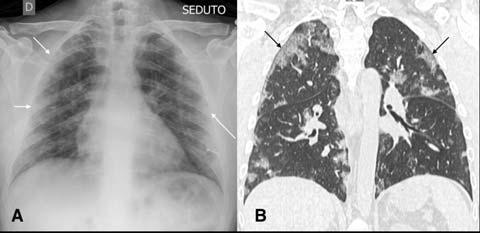

Fig 1 — CXR (A) and CT (B) images of a 45-year-old male who presented with fever and cough. He had hypoxia and leukopenia on examination and his nasal swab was positive for SARS COV-2. CXR shows bilateral blurred opacities with unclear vascular margins (white arrow) with corresponding ground glass changes in the CT (black arrows). Images reproduced with permission from Covid-19 Database of the SocietaItaliana di Radiologia Medica e Interventistica.